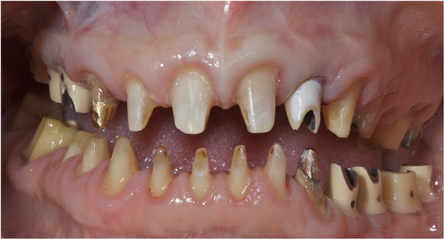

This patient previously presented with esthetic concerns but was reluctant to proceed with reconstructive dental treatment (Figure 19 and Figure 20). She had been monitored for several years and advised of the benefits of an interdisciplinary treatment plan including periodontal, dental implant, and prosthodontic therapy. The diagnosis included occlusal trauma, loss of vertical dimension, lack of posterior tooth support, and supra-eruption. There was also gingival asymmetry, lack of attached gingiva, lateral ridge defect for the mandibular left molar region, pneumatization of the maxillary right sinus, and alloy tattoo of the gingiva for the maxillary right bicuspids. Eventually the mandibular left second bicuspid, which was an abutment for a fixed partial denture, fractured, resulting in an abscess and significant bone loss localized to this abutment tooth (Figure 21). At this point, given the need for extraction and now more limited posterior chewing capability, the patient requested a comprehensive consultation and treatment plan for the reconstructive therapy she had previously elected to postpone.

Figure 19 This patient presented with esthetic and functional concerns, but was reluctant to proceed with reconstructive dental treatment.

Figure 19